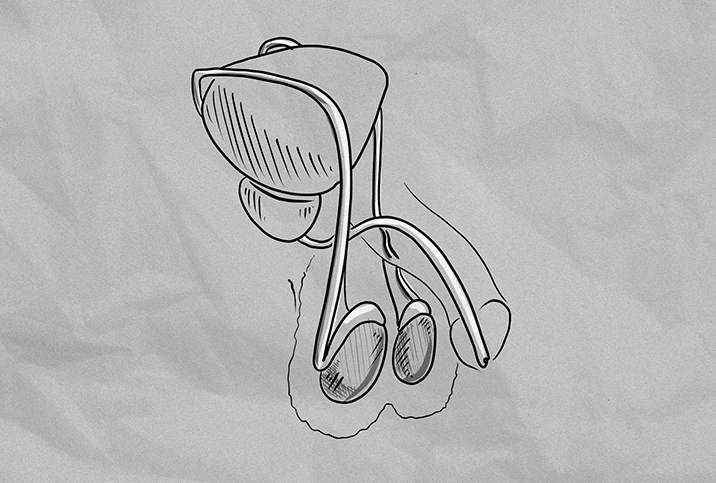

The Testicular Cancer Awareness Foundation provides the following four-step process for a testicular self-exam during or after a warm shower:

- Cup one testicle at a time using both hands.

- Roll the testicle between your thumb and fingers, using slight pressure.

- Get a feel for your spermatic cord and epididymis tube, which connect on the backside of the testicle.

- Feel for lumps or changes in size or consistency.